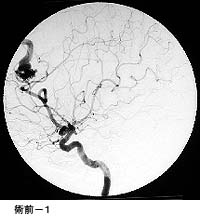

(2)脳動静脈奇形に対する液体塞栓物質を用いた治療

*治療により異常血管は閉塞されました。